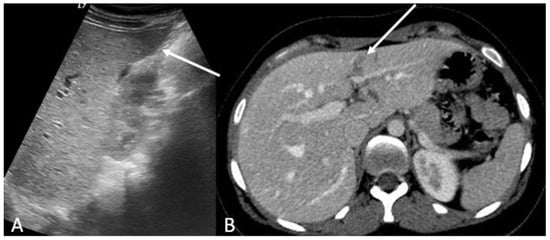

- Brillantino, A.; Iacobellis, F.; Festa, P.; Mottola, A.; Acampora, C.; Corvino, F.; Del Giudice, S.; Lanza, M.; Armellino, M.; Niola, R.; et al. Non-Operative Management of Blunt Liver Trauma: Safety, Efficacy and Complica-tions of a Standardized Treatment Protocol. Bull. Emerg. Trauma 2019, 7, 49–54. [Google Scholar] [CrossRef] [PubMed]

- Brillantino, A.; Iacobellis, F.; Robustelli, U.; Villamaina, E.; Maglione, F.; Colletti, O.; De Palma, M.; Paladino, F.; Noschese, G. Non operative management of blunt splenic trauma: A prospective evaluation of a standardized treatment protocol. Eur. J. Trauma Emerg. Surg. 2016, 42, 593–598. [Google Scholar] [CrossRef]

- Romano, L.; Giovine, S.; Guidi, G.; Tortora, G.; Cinque, T.; Romano, S. Hepatic trauma: CT findings and considerations based on our experience in emergency diagnostic imaging. Eur. J. Radiol. 2004, 50, 59–66. [Google Scholar] [CrossRef]

- Coccolini, F.; Panel, T.W.E.; Coimbra, R.; Ordonez, C.; Kluger, Y.; Vega, F.; Moore, E.E.; Biffl, W.; Peitzman, A.; Horer, T.; et al. Liver trauma: WSES 2020 guidelines. World J. Emerg. Surg. 2020, 15, 24. [Google Scholar] [CrossRef]